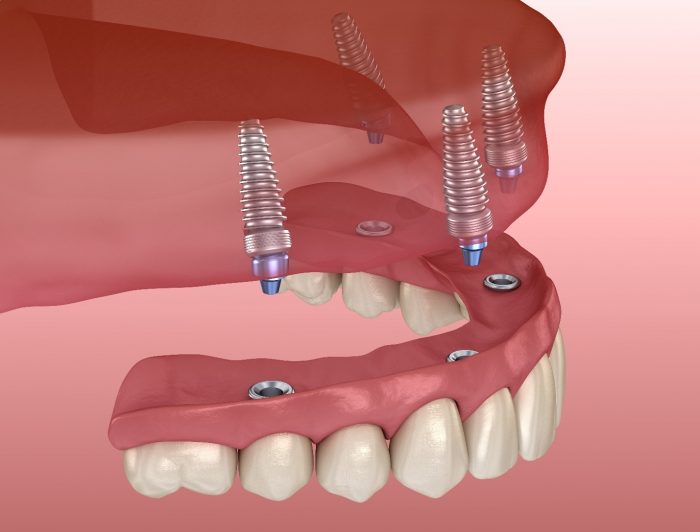

Dentist That Do Implants Near Me

Visiting a dentist that do implants near me requires an adequate preparation so that you will be able to get the best result. Call our Dental implants dentist in Houston.

Visiting a dentist that do implants near me requires an adequate preparation so that you will be able to get the best result. Call our Dental implants dentist in Houston.